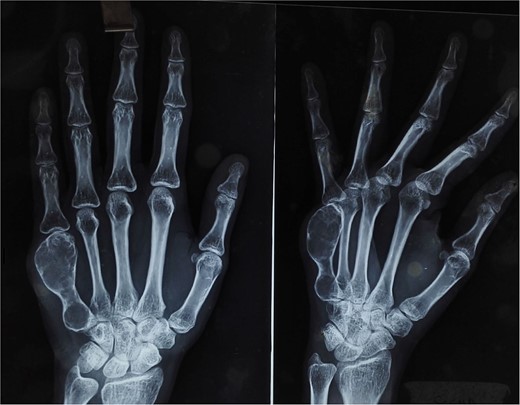

At 2 years postoperatively, the patient showed excellent functional outcomes. Radiographs demonstrated a stable MCP joint with well-preserved joint space, indicating successful graft incorporation (Fig. 3). Donor site radiographs at 2 years showed appropriate spacing between the third and fifth metatarsals with no evidence of arch collapse or stress reaction in the adjacent bones (Fig. 4). The patient achieved an active MCP joint range of motion of 0–80 deg (Fig. 5).

Post-operative radiograph showing preserved joint space and structure of transferred metatarsal.